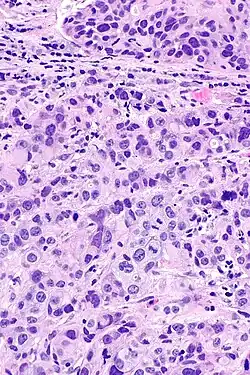

Inwazja warstwy mięśniowej raka urotelialnego

Inwazyjny (naciekający) rak urotelialny jest definiowany jako obecność inwazji nowotworowej poniżej błony podstawnej urotelium[74]. Makroskopowo inwazyjne nowotwory urotelialne mogą przyjmować formę brodawkowatą, polipowatą, guzkową, litą, tworzyć rozlany naciek ściany pęcherza moczowego. Zmiany mogą występować pojedynczo lub wieloogniskowo[75]. Typowo większość guzów pT1 jest brodawczakowata o niskim lub wysokim stopniu złośliwości histologicznej, z kolei guzy o większym zaawansowaniu pT2–T4 wykazują morfologię niebrodawczakowatą i cechują się wysokim stopniem złośliwości[76][77].

Mikroskopowo w utkaniu obecne są komórki tworzące gniazda, sznury komórek lub pojedyncze komórki pooddzielane desmoplastycznym podścieliskiem[76][78]. Możliwy jest bardziej rozlany wzór wzrostu nowotworu, w którym komórki tworzą arkusze, przy czym również w takim utkaniu spotyka się ogniskowo występujące gniazda komórek[78]. Komórki cechują się umiarkowaną do obfitej ilością amfofilnej lub eozynofilnej cytoplazmy i dużym hiperchromatycznym jądrem komórkowym. Jądra komórkowe wykazują znaczną pleomorficzność, nieregularne, kanciaste granice. Liczba i wygląd jąderek wykazuje znaczną zmienność. Gniazda komórek nowotworowych zwykle indukują reakcję desmoplastyczną podścieliska. Obecne są liczne figury mitotyczne i możliwa jest obecność nieprawidłowych figur mitotycznych. W podścielisku większości guzów jest obecny naciek limfocytów i komórek plazmatycznych, naciek najczęściej jest wyrażony ogniskowo od łagodnego do umiarkowanego stopnia, ale może być nasilony i rozlany[76][78]. Może być widoczna inwazja naczyń[78].

Kluczowym elementem wpływającym na rokowanie jest głębokość nacieku nowotworowego. Początkowo inwazja blaszki mięśniowej właściwej może przebiegać jako obecność pojedynczych komórek, klastry lub gniazda komórek w górnych warstwach blaszki mięśniowej właściwej, zwykle skojarzonej z infiltracją komórek zapalnych[79]. W późniejszych etapach inwazji obecne są klastry lub rozlane arkusze komórek nowotworowych w obrębie blaszki mięśniowej właściwej[79].